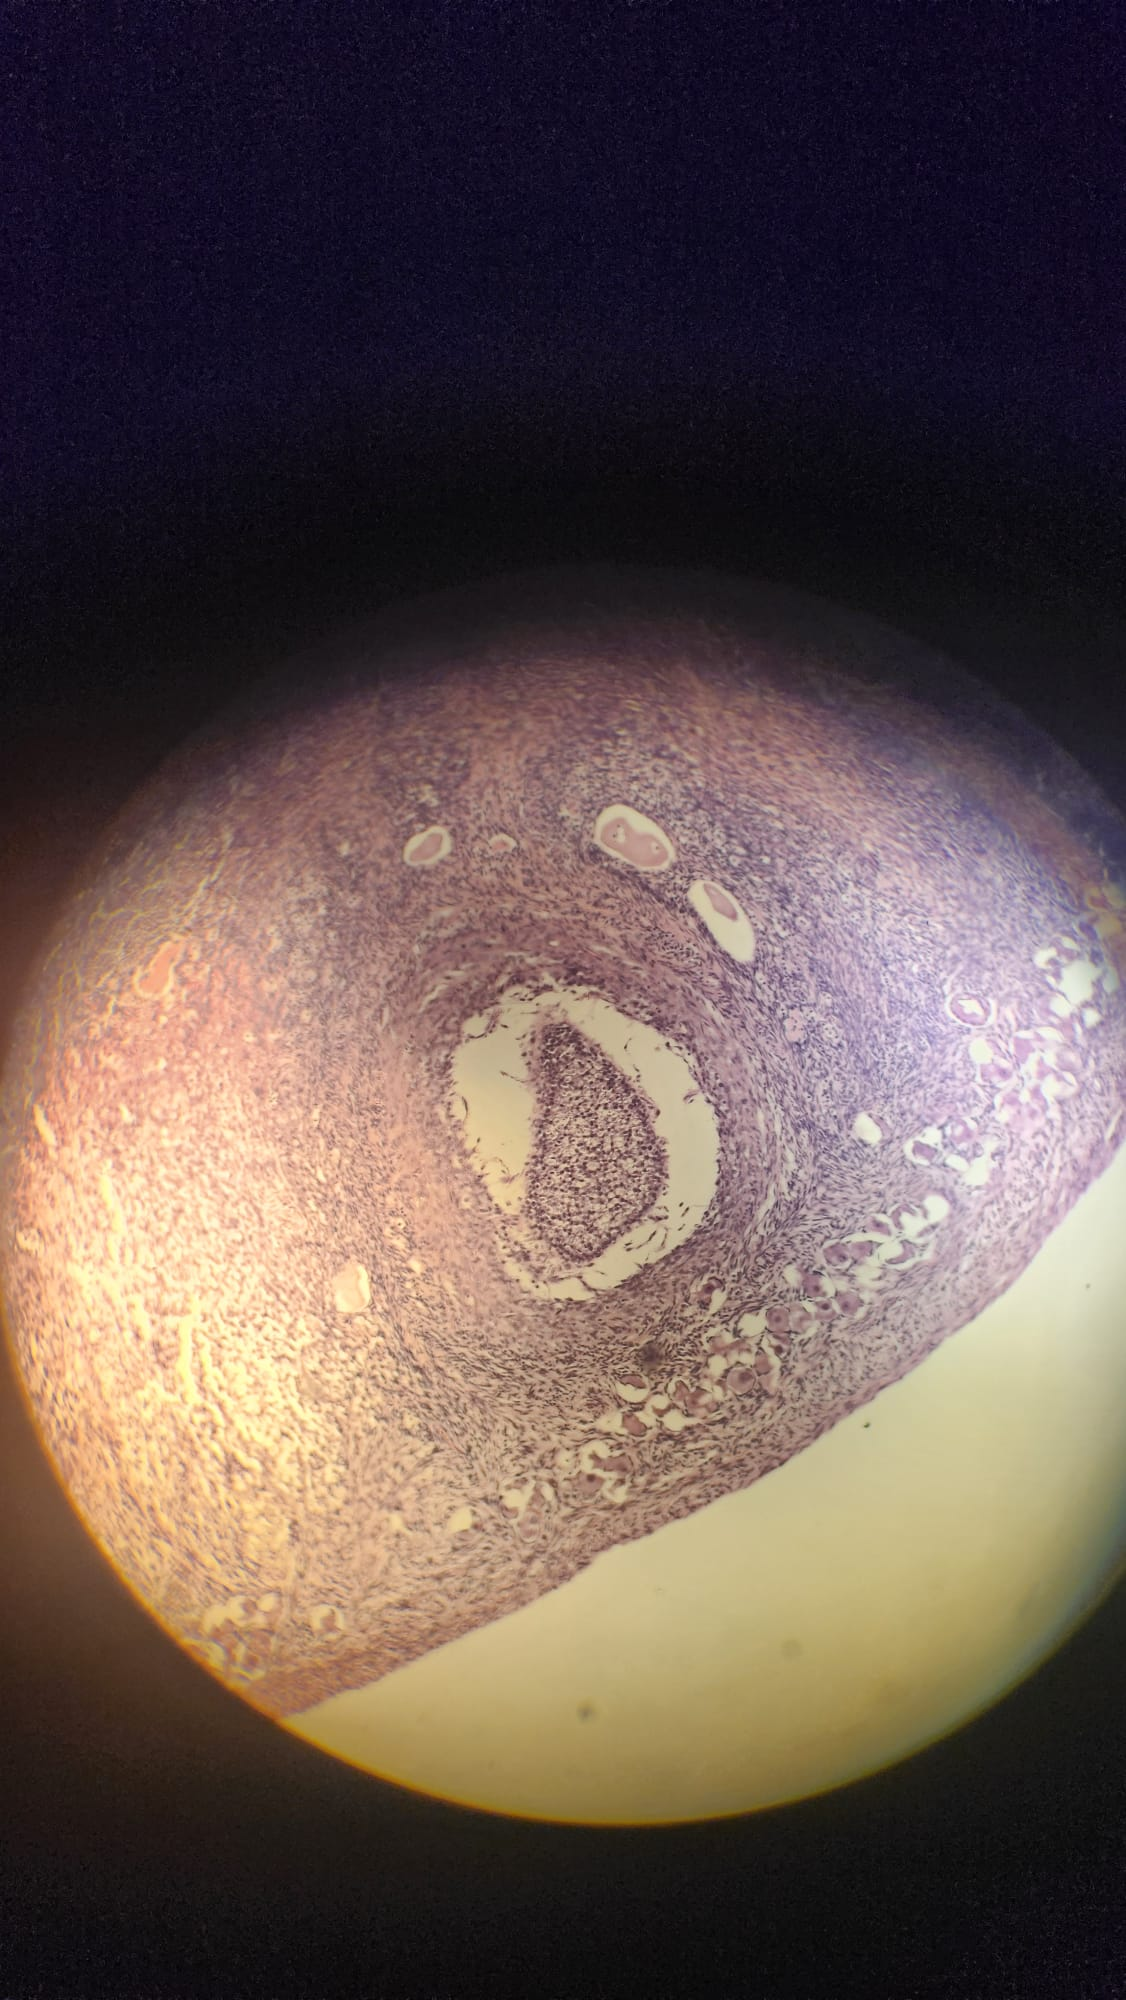

What are the 2 round structures seen here?

Renal corpuscles (glomerulus + Bowman’s capsule)